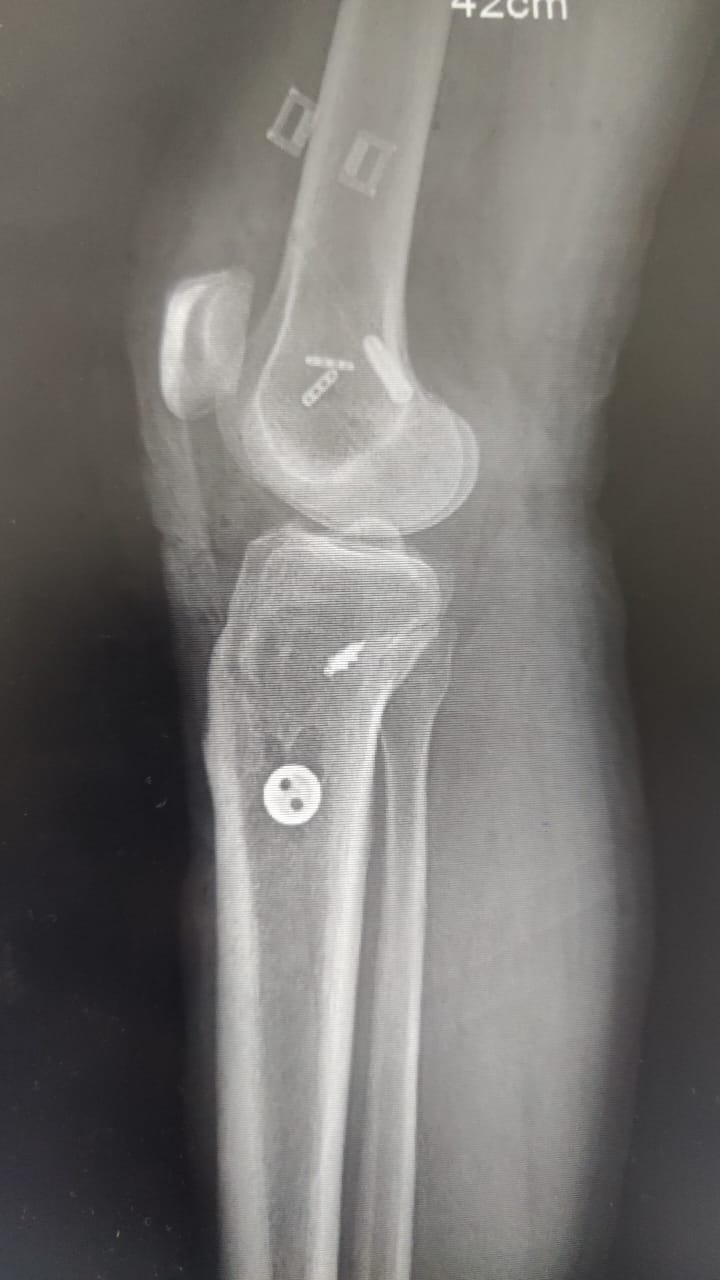

- Knee Replacement Surgery